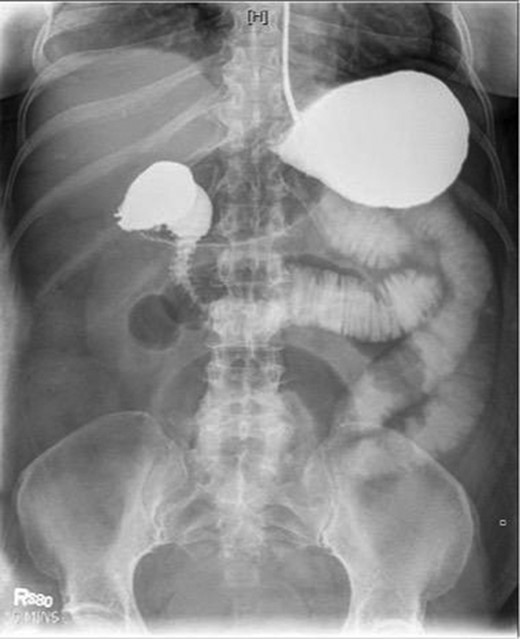

Laboratory studies were remarkable for leukocytosis, and an elevated lactate that improved with hydration (Fig. 1), while urinalysis was unremarkable. Abdominal CT scan obtained at this time demonstrated a partial SBO in the mid-small bowel as well as inflammation and thickening of the duodenum. A small bowel series was ordered, and showed high grade SBO (Figs 2–5).

Fluoroscopic barium study demonstrating oral contrast agent progression through the small bowel at 5 h after ingestion. Dilated bowel loops can be visualized throughout the abdomen, and transit time is delayed. Impression—high-grade distal small bowel obstruction.